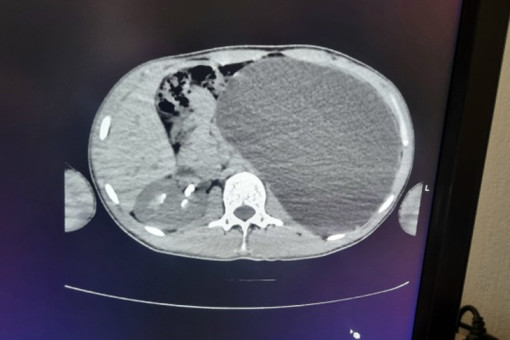

До проведения медосмотра патология никак не проявлялась — 17-летний парень юноша чувствовал себя здоровым и никогда не жаловался на проблемы с почками. После того, как в кабинете УЗИ было выдано заключение: «объемное образование, размер невозможно измерить, левой почки нет», пациент сразу был направлен в стационар детской городской клинической больницы № 1.